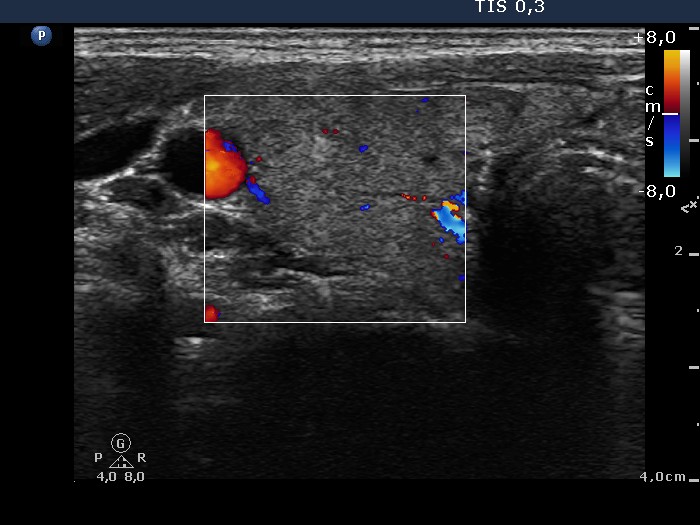

Graves' disease - Case 1049

Follow-up investigation 36 months after first visit (ultrasonographic picture 3)

Patient on daily 10 mg methimazole therapy in euthyroid state

Right lobe, transverse scan, color Doppler mode. The vascularization became decreased.